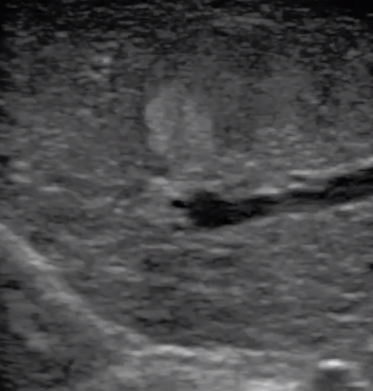

腹腔鏡下 肝臟占位

腹腔鏡超聲是超聲技術(shù)和腹腔鏡技術(shù)的融合,腹腔鏡超聲降低了對(duì)超聲探測(cè)深度的要求。由微小切口進(jìn)入手術(shù)部位,多角度彎曲可選擇,降低手術(shù)難度及風(fēng)險(xiǎn);與受檢組織器官直接接觸,有效避免氣體干擾。

應(yīng)用科室:麻醉科、手術(shù)室、普外科、泌尿外科、婦產(chǎn)科、腫瘤科、介入科等